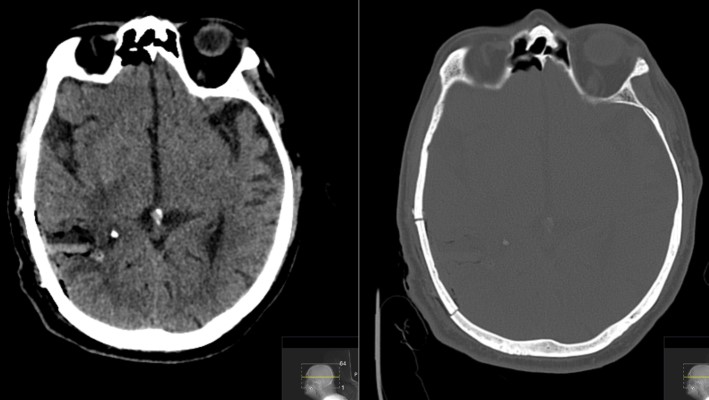

This is a 69 year old male with a known history of renal cell carcinoma who presented with cognitive decline and a neck mass.He had memory issues which were attributed to chemotherapy. He also was having new headaches. The neck mass was due to an infection. Neurologic examination was relatively unremarkable.